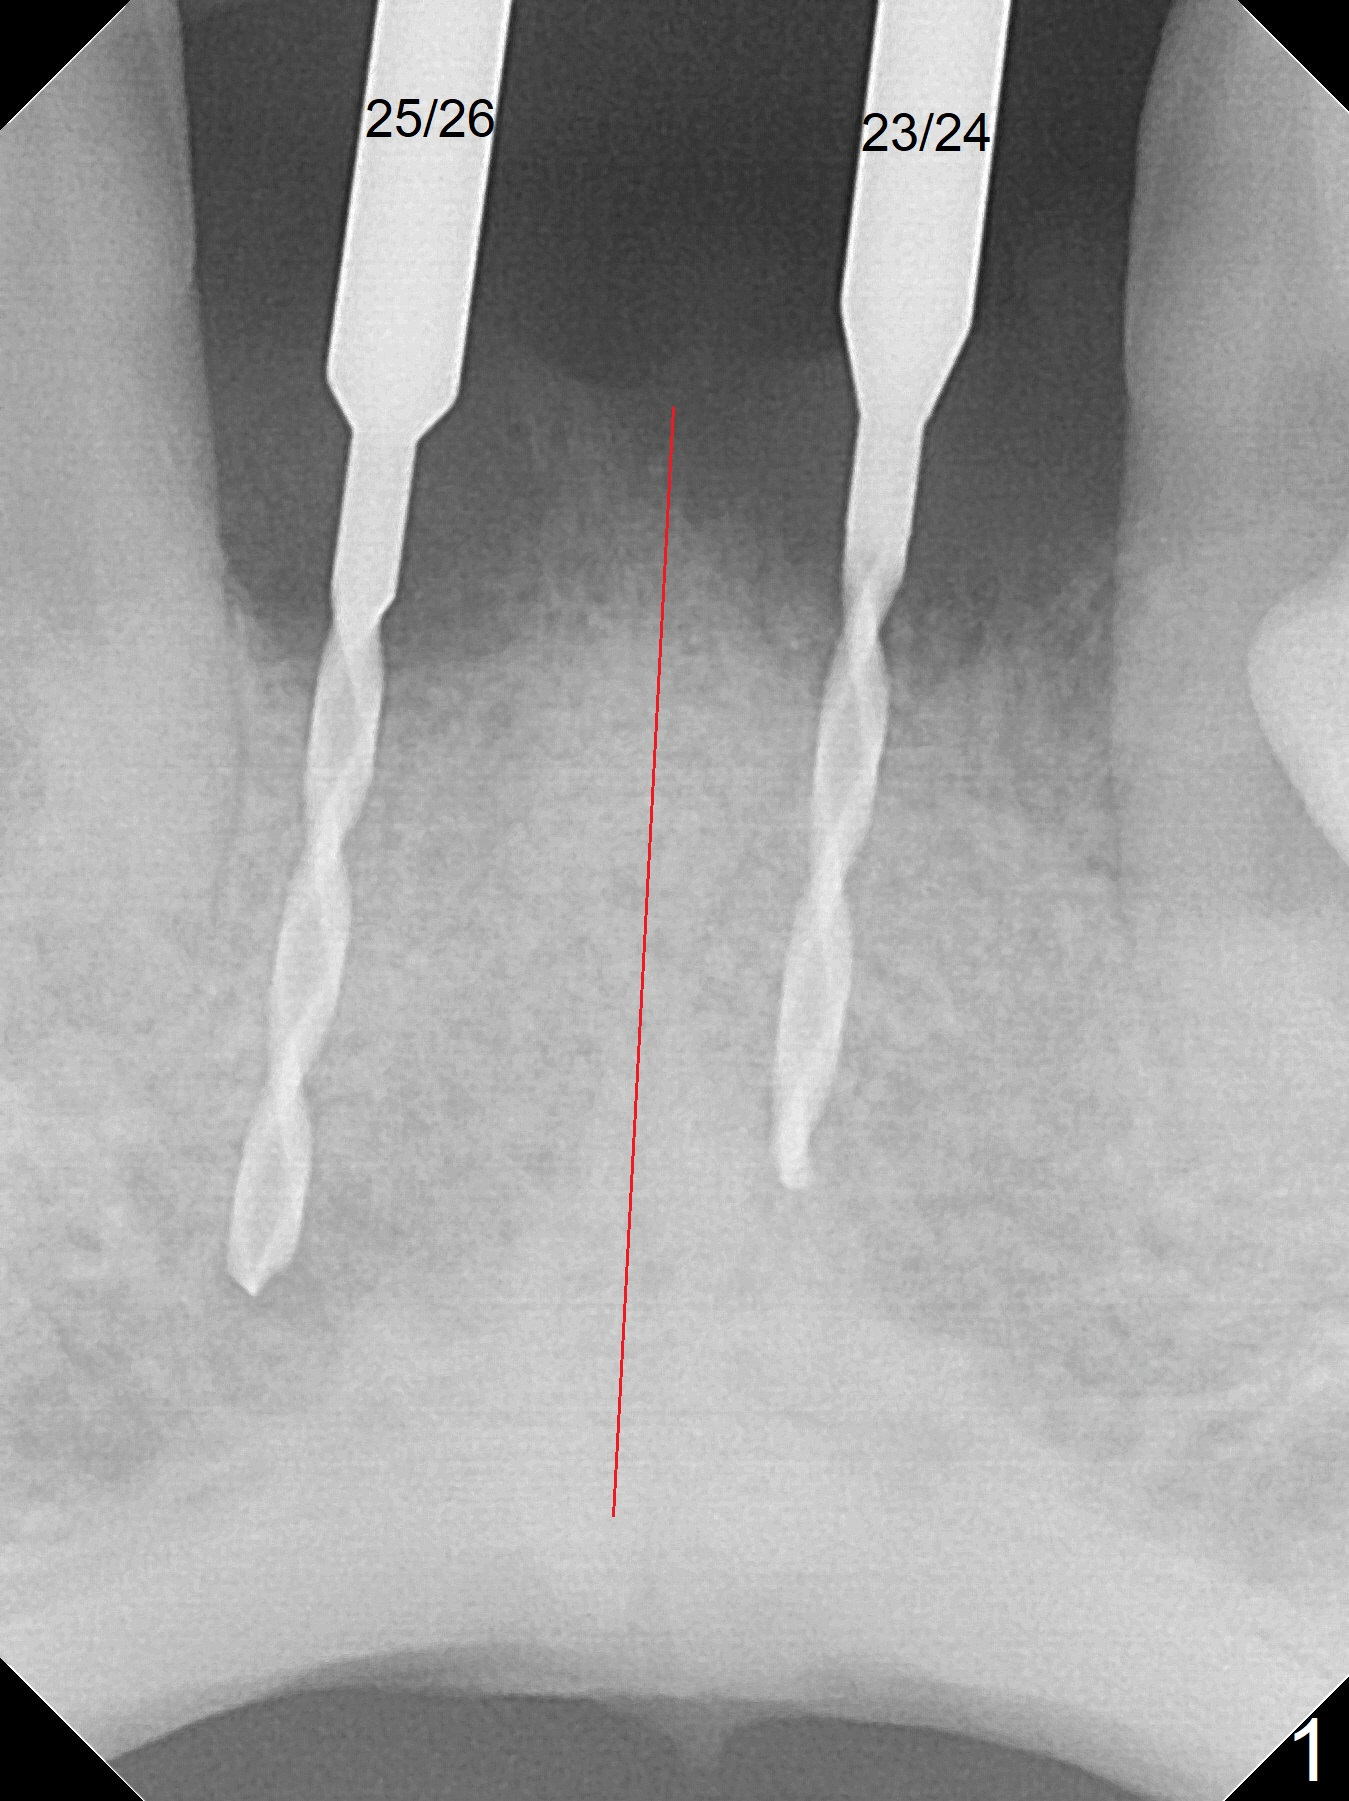

After extraction of 4 of the lower incisors, there are basically 2 sockets (#23/24 and 25/26), separated by the apparently midline bone (Fig.1 red line).  In spite of using Lindamann bur to move the 25/26 osteotomy mesially, a 3x14(2) mm dummy implant remains close to the tooth #27 (Fig.2).  The terminal branch of the Incisive Canal (<) is located between the lateral and central incisors.  A de novo osteotomy (Fig.3 (1.5 mm drill)) is made mesial to the original one (O).  While the 3x14(2) mm dummy implant is incompletely placed at #25/26, a 3x14(4) mm 1-piece one is placed at #23/24 (Fig.4).  Finally the same implant is placed at #25/26 with placement of mineralized cortical/cancellous bone (Fig.5 *).  When the large sockets are sutured, the supraerupted teeth #7-9 touch the lower gingiva (Fig.6).  The incisal edge is reduced for clearance (Fig.7).  Periodontal dressing is less likely to be dislodged with the incisal edge reduction (Fig.8,9).  A provisional FPD is fabricated 1 week postop.  Hard (Fig.10) and soft (Fig.11,12) tissues heal 5.5 months postop.  The patient returns for crown cementation 3 months post impression (9 months postop, Fig.13,14).